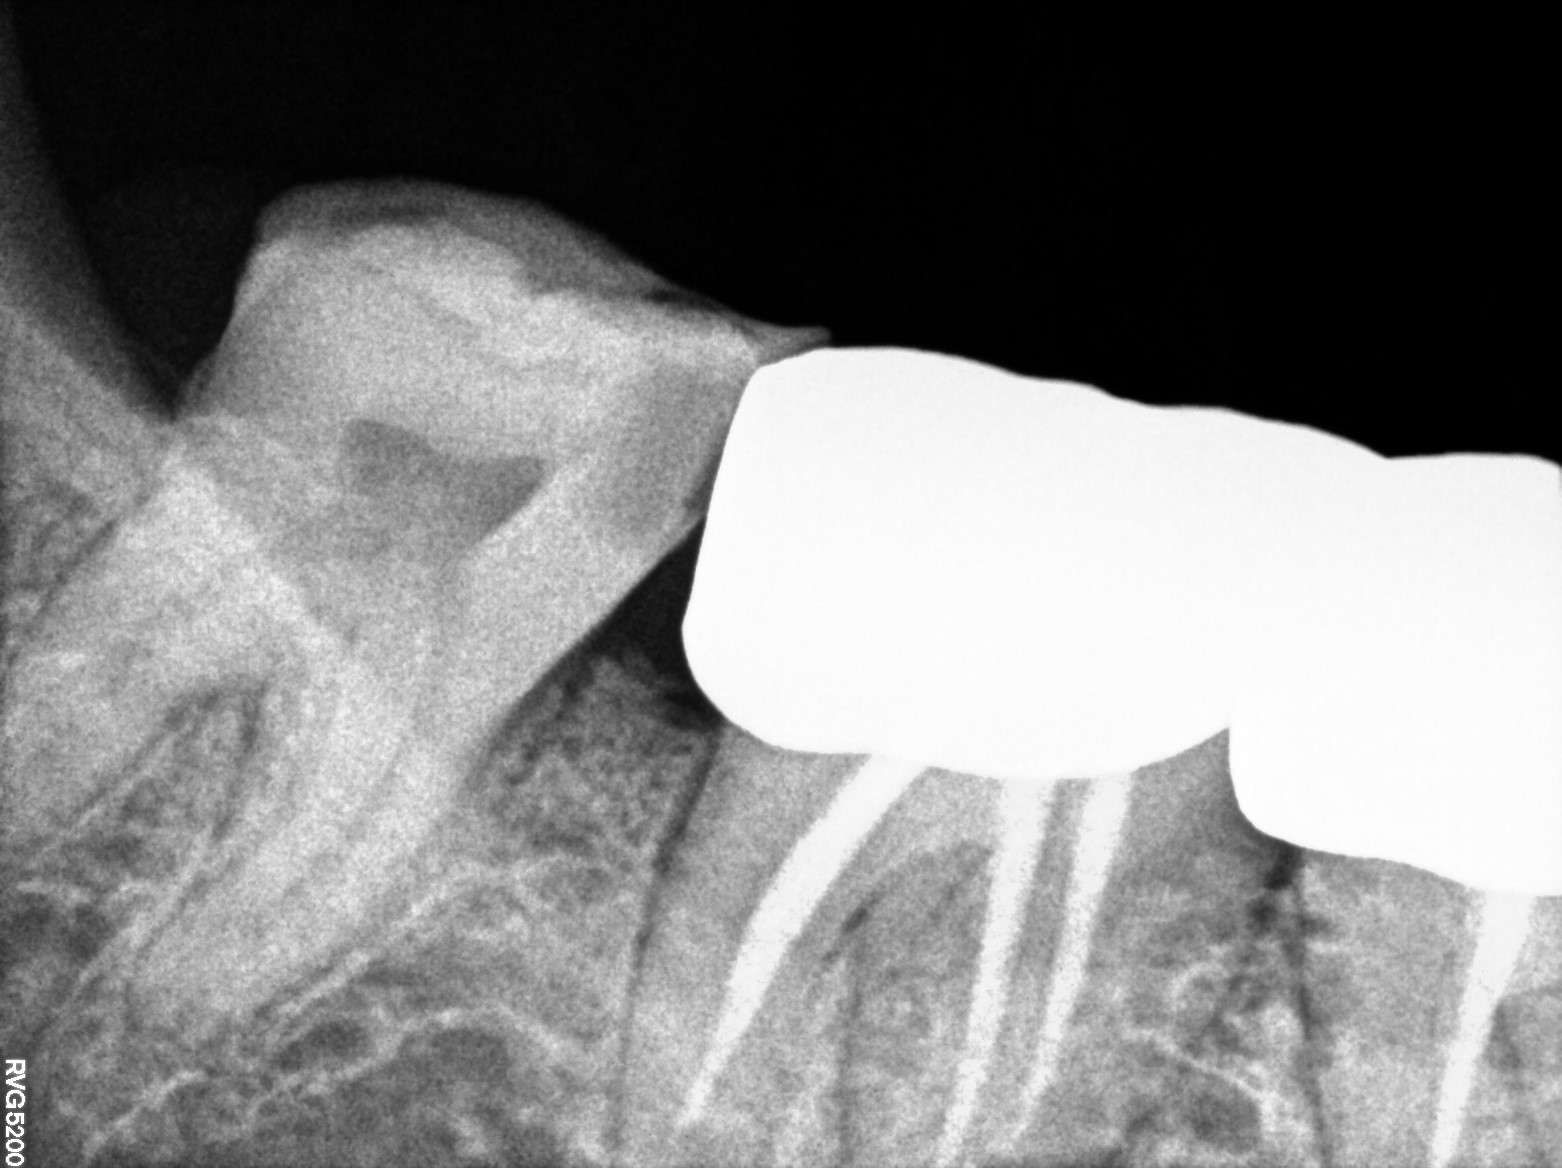

Dental Radiographs FHIR: DocumentReference · LOINC 24641-7

2 (1).jpg

24641-7